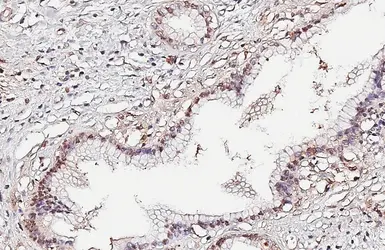

Anti-p53 antibody [DO1] used in IHC (Paraffin sections) (IHC-P). GTX70214

GTX70214 IHC-P Image

p53 antibody [DO1] detects p53 protein at nucleus by immunohistochemical analysis.

Sample: Paraffin-embedded human pancreatic cancer.

p53 stained by p53 antibody [DO1] (GTX70214) diluted at 1:100.

Antigen Retrieval: Citrate buffer, pH 6.0, 15 min

2 / 14